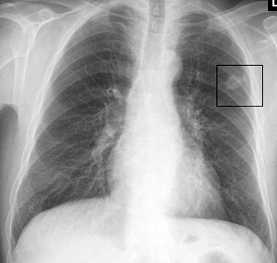

Обратите внимание на увеличение и нарушение структуры корня правого легкого. Это центральный рак. Кроме того, выявлены очаговые тени в обоих легочных полях (гематогенное распространение), а также «лучи», идущие радиально от опухоли корня (лимфогенное распространение).